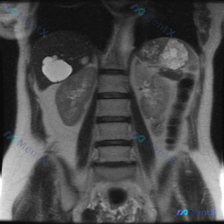

今天看到一个很有意思的案例,很能体现影像阅片里的「思维陷阱」,整理出来和大家一起理一理思路。 --- 先看「初始诉求」与「影像事实」的冲突 用户明确问的是「脾脏病变」,但点开图像发现——这根本不是上腹部的图像,而是一张 胸腰段脊柱区域的 MRI T2 加权冠状位。 这是第一个关键点:不能被临床申请单...

刚看到一份有意思的影像资料:提问是“脾脏病变”,但提供的分析却完全是肾脏MRI T2加权冠状位的内容。整理了一下思路和发现,和大家讨论。 --- 先理清楚最核心的矛盾 首先必须明确:基于现有给出的影像信息,完全无法评估脾脏。 报告里只描述了双肾、肾盂肾盏、肾周间隙,压根没提脾脏的大小、信号或结构——...